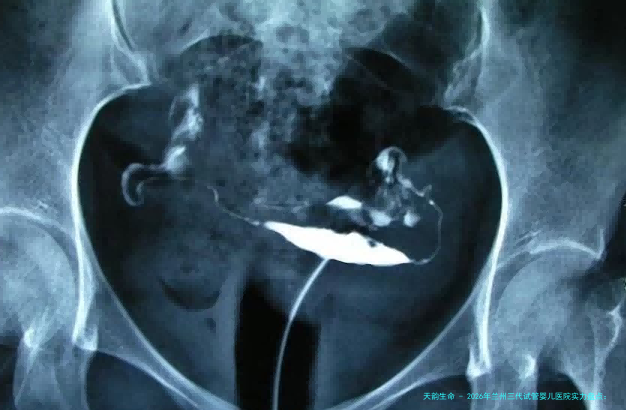

通往新生命的道路须要科学、耐烦和无误的选择。以上就是“2026年兰州三代试管婴儿医院力量盘查:技术、资质与全剖析,附规范机构选择手册”,这一些医生均来自正规医院,拥有丰盛临床经验和精湛技术,声誉经得起市场检验。想查阅医生图片例子、网上面诊、认识医生,咨询本站客服,获取一双一专用客服交流服务!